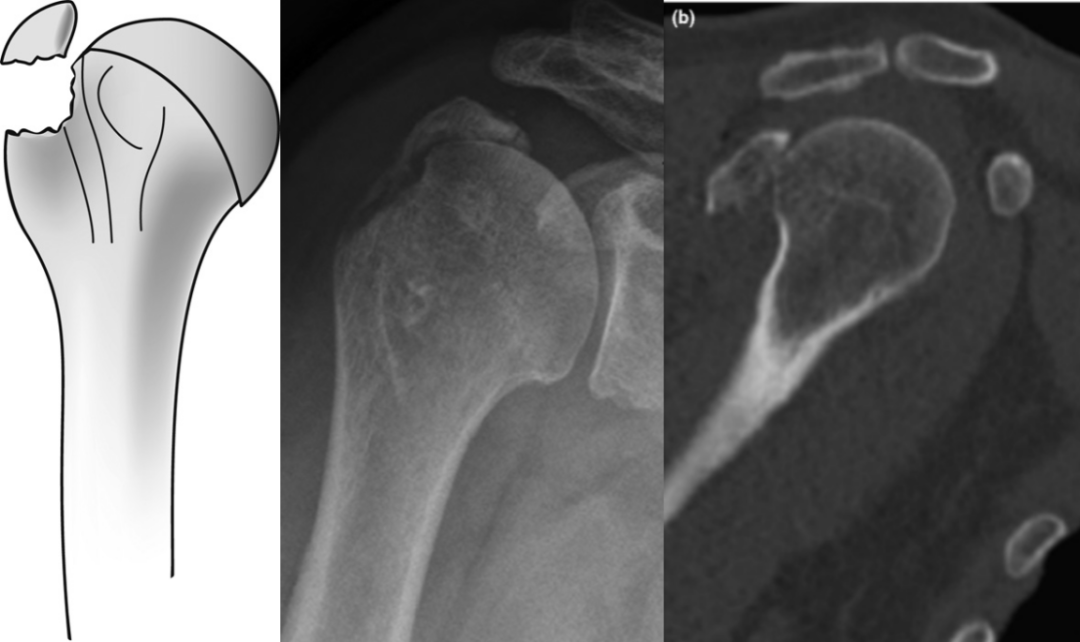

Bahrs等(2006年)提出大结节骨折的三种致伤机制:撕脱机制、肩峰撞击机制和关节盂缘撞击机制。Mutch等(2014年)在此基础上进一步提出基于骨块形态的分类系统:

撕脱性骨折:特征为水平向骨折线伴小骨块分离;

图3 doi:10.1302/0301-620X.96B5.32362

劈裂性骨折:以垂直向骨折线及单一较大骨块为典型表现;

图4 doi:10.1302/0301-620X.96B5.32362

压缩性骨折:因大结节与关节盂或肩峰撞击导致骨块向肱骨头内凹陷。

图5 doi:10.1302/0301-620X.96B5.32362